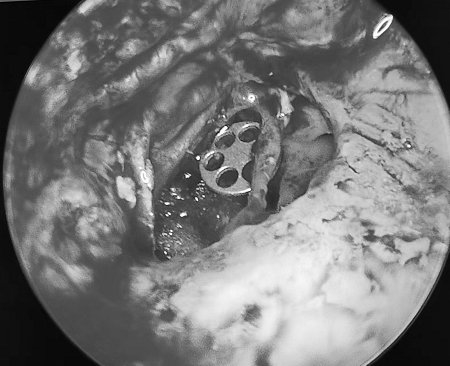

随着近些年科学技术的进步,目前大多数听骨链重建手术均可以在耳内镜下完成,与显微镜手术相比,内镜手术可以提供更好的视野,有时可以提供更清晰的图像,因为内镜可以深到深部空间,所以可以减少不必要的骨质去除和减少皮肤的缺口。可以在清除中耳病变的同时一起完成听骨链重建,有效改善患者的听力。

image007

自体听骨植入